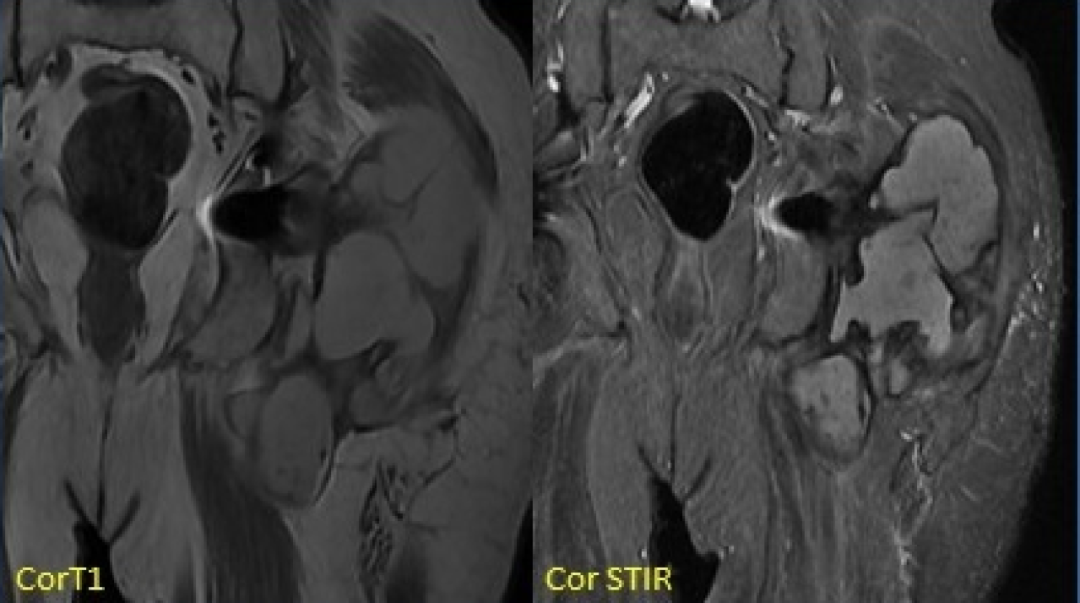

5. Metal-on-metal(MOM)disease:

假性滑囊,是金属对金属髋关节置换的组织反应;表现为髋关节假体周围的滑囊。最常见的部位是:髋臼上缘、大粗隆和小粗隆。

人工髋关节置换术。假体周围囊性肿块(箭头)